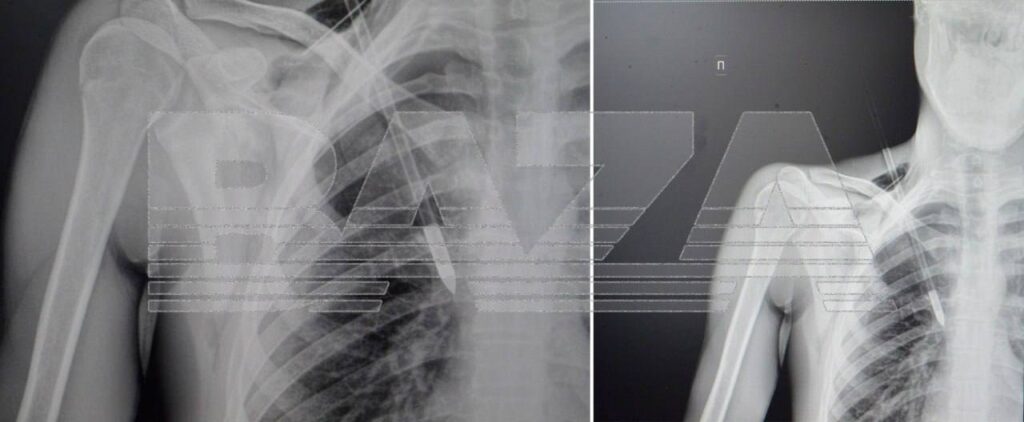

O, oxu atıb, ox ağacdan rikoşet edib və körpücük sümüyü ilə birinci qabırğa arasına girib, ağciyəri dərin şəkildə zədələyib.

Qan damarları yaradan cəmi millimetr məsafədə yerləşirdi, bu isə ölümcül qanaxmaya səbəb ola bilərdi.

O, təcili olaraq xəstəxanaya çatdırılıb, burada cərrahlar oxu ehtiyatla çıxarıblar, ağciyəri tikiblər və drenaj quraşdırıblar.